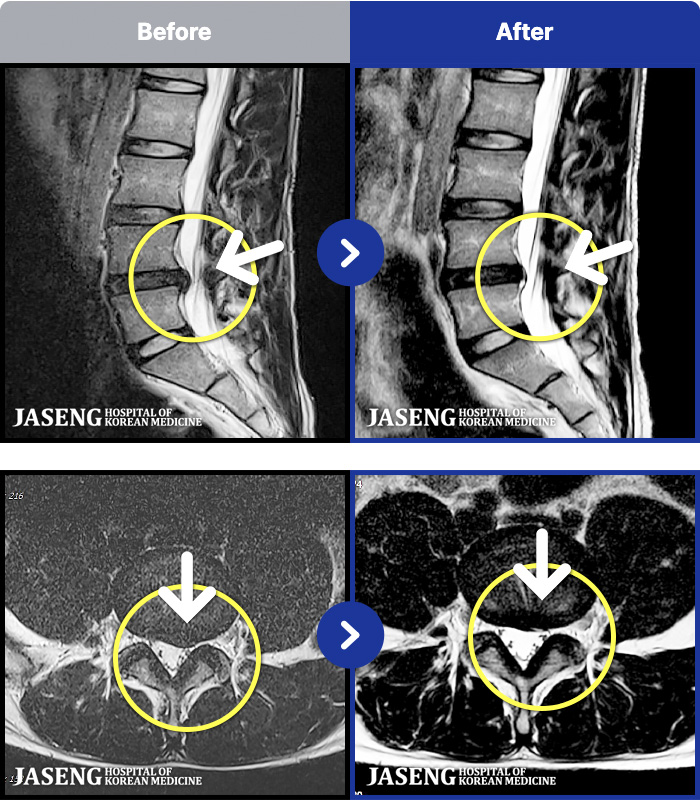

MRI ũ ʸ Ȯϼ.